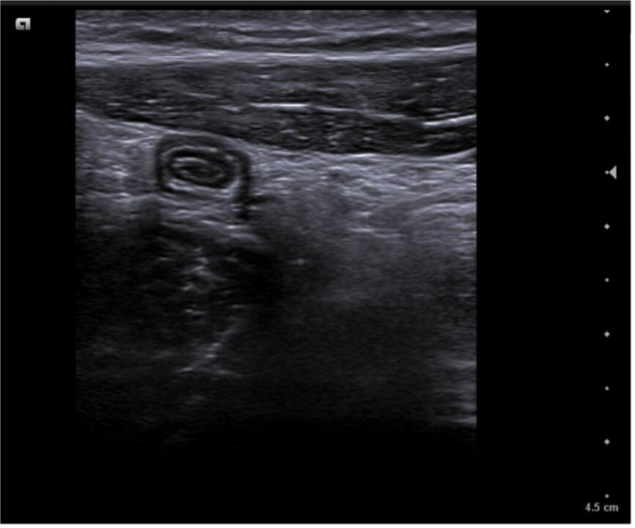

Caso 1. Asa intestinal en FID con poca movilidad (vista con sonda lineal) posible apendicitis.

Caso 2. Asa intestinal fija con edema de pared por posible apendicitis o ileitis. Corte transversal con signo del donut.